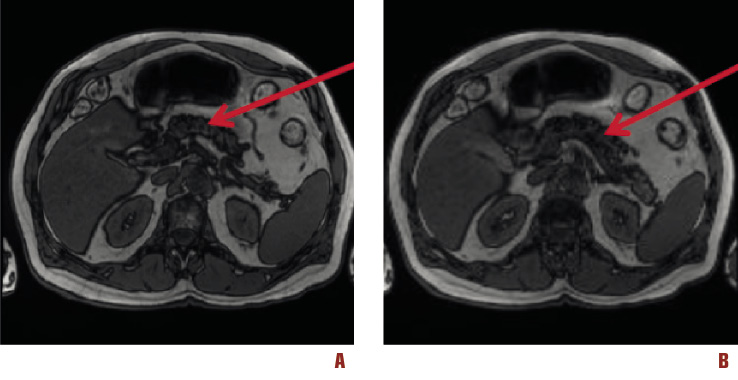

In 2018, after 38 years from the first finding of hyperenzymemia, the magnetic resonance imaging (MRI) findings of the upper abdomen revealed: liver containing some small cystic formations scattered in both lobes, the greatest being 10 mm large; pancreas within limits; some bilateral renal cystic cortical formation, greater than 17 mm; no areas of pathological enhancement after paramagnetic contrast medium infusion (gadoteridol) of the upper abdomen organs. The magnetic resonance cholangio-pancreatography (MRCP) [2] showed no biliary lithiasis, no dilatation of the intrahepatic biliary tree, hepato-choledochus with a maximum caliber of 7 mm, regular Wirsung duct (Figure 4).

Figure 4. Findings from magnetic resonance cholangio-pancreatography (MRCP) performed in 2018. The arrows indicate normal pancreas (A and B).